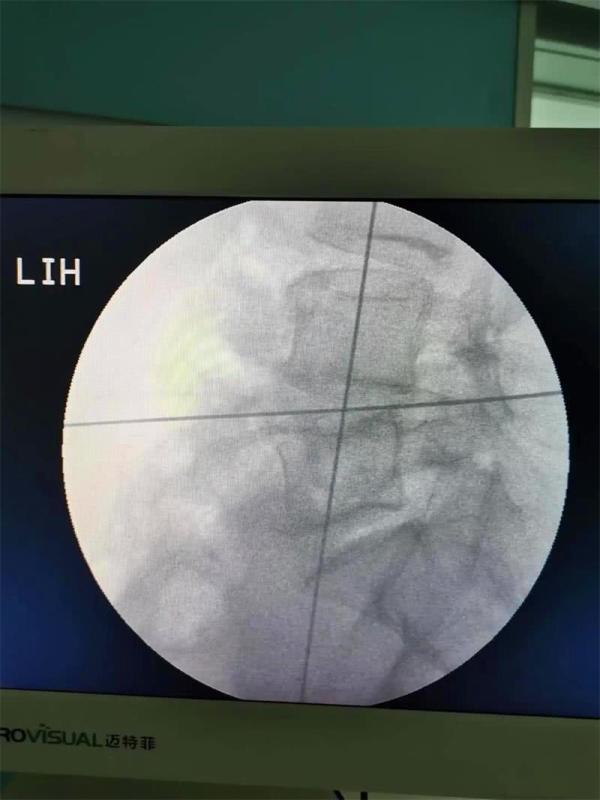

昆明市中医医院骨伤科关上病区在江苏省中医医院(南京中医药大学附属医院)骨伤科主任陈刚的指导下,5月中旬,顺利完成2例腰椎微创新技术——腰椎斜向椎体间融合术(OLIF)。并通过网络会议形式开展了“OLIF的相关问题和体会”的学术交流活动。

通过不到5cm的小切口,切除了椎间盘并植入大尺寸融合器,手术出血不到10毫升。术后当天,患者就感觉腰腿痛明显缓解,术后第2天已经能下床行走。该项技术的成功实施,标志着昆明市中医医院骨伤科脊柱微创水平再上新台阶。